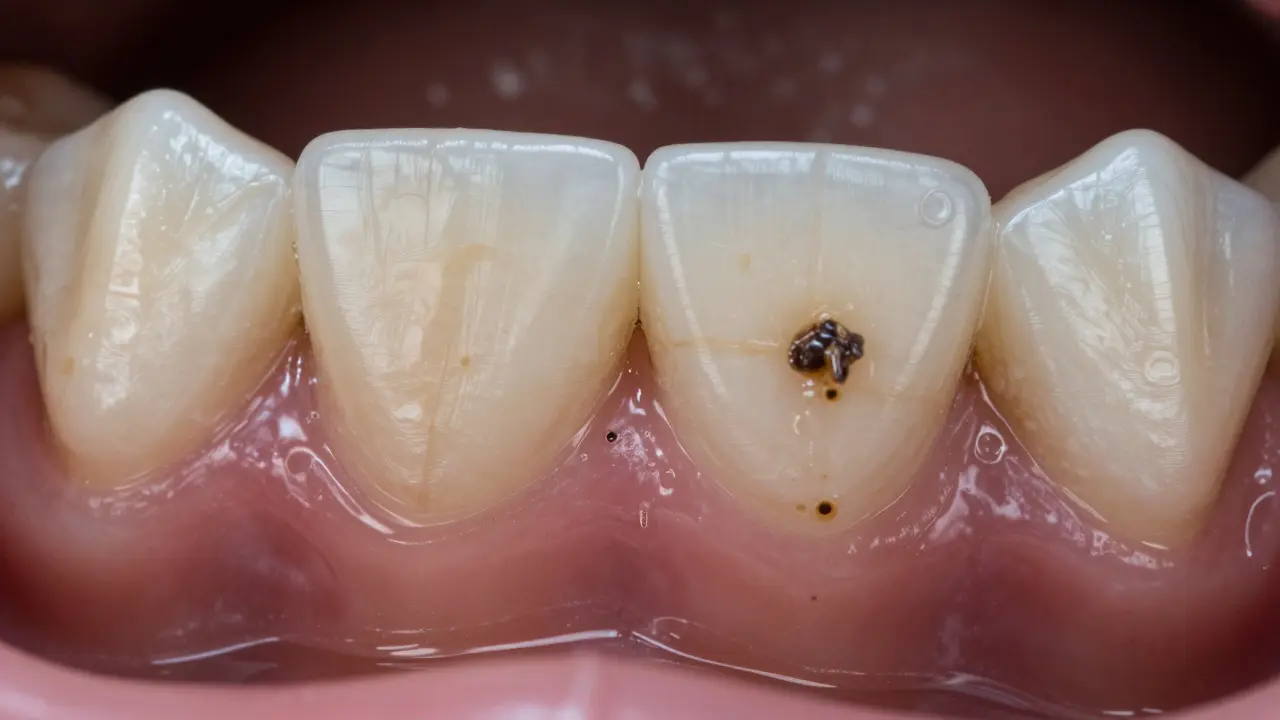

Černý zubní kámen není jen estetický problém. Když si v zrcadle všimnete tmavých skvrn na zubech, zejména u základny zubů, nejde o náhodnou skvrnu. Je to hromadění bakterií, potu a chemických látek, které se postupně ztuhly na povrchu zubů. Ačkoli se často mylí, že to je jen vina špatné hygieny, příčiny jsou složitější - a některé z nich vás překvapí.

Zubní kámen je ztuhlá vrstva plaku, která se vytváří, když bakterie na zubech nejsou pravidelně odstraněny. Plak je měkká, lepkavá vrstva, ale když zůstane na zubech déle než 24-72 hodin, začne vápník a jiné minerály z sliny vytvářet tvrdou, neodstranitelnou vrstvu - kámen. Většina lidí má zubní kámen bílou nebo žlutou, ale u některých se barví na černo. To se děje kvůli konkrétním látkám, které se do něj vážou.

Proč se černý kámen objevuje především na spodních předních zubech?

Nejčastěji se černý zubní kámen vyskytuje na vnitřní straně spodních předních zubů. Proč? Protože tam vylučuje slina z větších slinných žláz - slinná žláza pod jazykem (sublinguální) a slinná žláza pod čelistí (submandibulární). Tyto žlázy vylučují slinu bohatou na minerály, které pomáhají ztuhnout plaku. Když k tomu přičteme časté pítí čaje nebo kávy, které se dostávají přímo do této oblasti, vzniká ideální prostředí pro tmavý kámen.

Porovnání zdravých zubů a zubů s černým kamenem, s doplňky stravy a nápoji v pozadí.